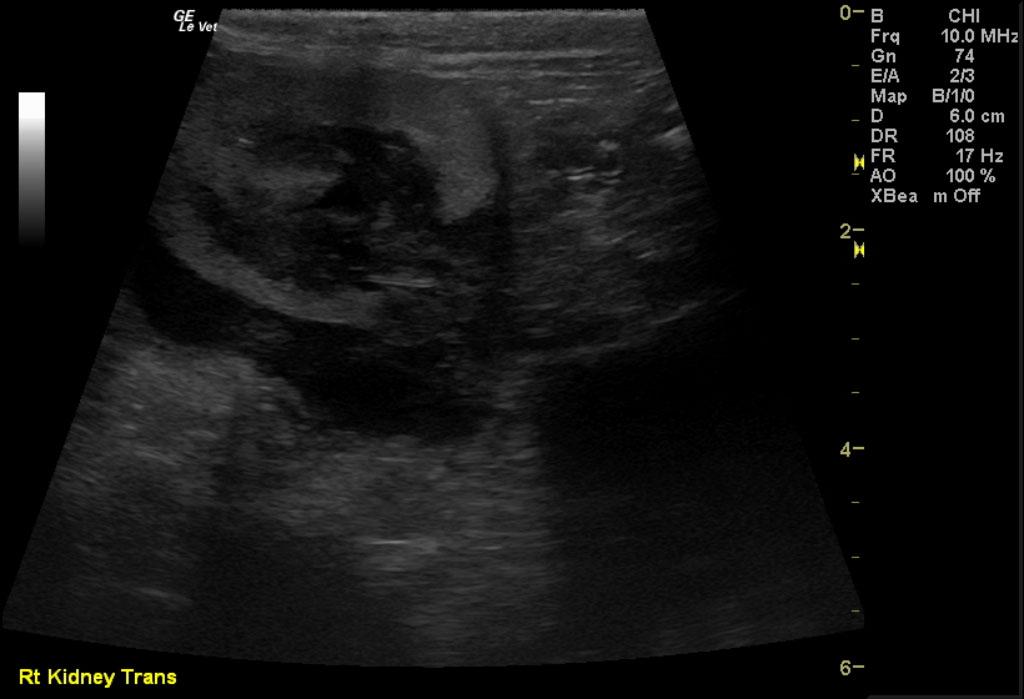

Image 1 & Video 1: The liver was moderately enlarged, rounded in shape having mildly hypoechoic echogenicity with multifocal hypoechoic and cystic nodules throughout. The gallbladder was normal in size, shape, and clean. Images 2-4 & Video 2-4: The left and right kidneys were severely enlarged with mild hydronephrosis in the right kidney. Both kidneys had hyperechoic cortices with large hypoechoic caps surrounding and invading the renal cortices (left kidney cap-7.4 mm in thickness, right kidney cap-13.6 mm in thickness). Image 5 & Video 5: Stomach: mucosal layer is mild/moderately thickened with overall wall thickness measuring 3.8 mm. Images 6: Intestine: there is focal mucosal layer thickening measuring up to 5.1 mm while the rest of the intestinal loops are of normal thickness. Video 6: Colon: the colonic wall appeared thickened at the ileocecolcolic junction. Image 7: Lymph Nodes: Multiple mesenteric lymph nodes were severely enlarged throughout the abdomen. The epigastric LN enlargement is shown in this image in the near field.